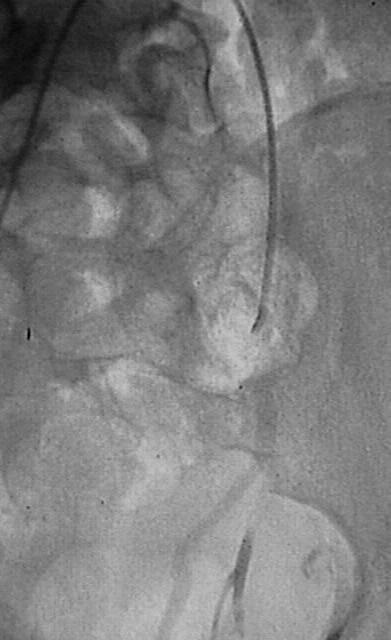

病例2:10岁 男孩 BIKE vs CAR后,发现盆腔搏动性肿物。ISS 27, BP 70

10岁 男孩 BIKE vs CAR后,发现盆腔搏动性肿物